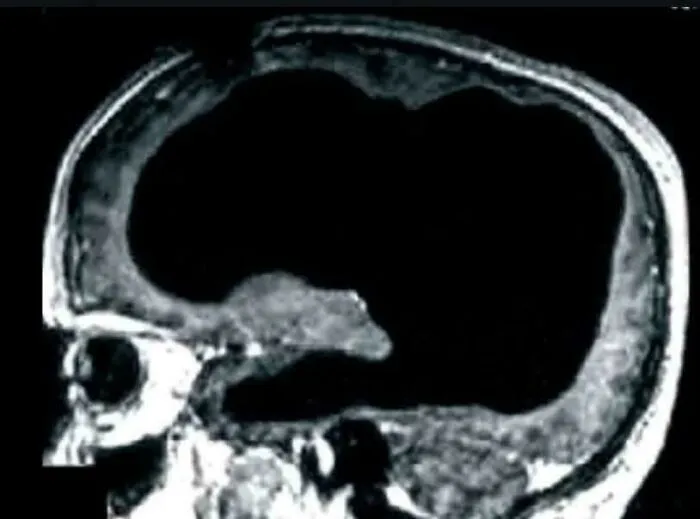

#3 Medicínska záhada

U istého muža zistili, že mu nevedomky chýba 90 % mozgu, no napriek tomu žil normálnym životom. Mužova lebka bola plná tekutiny, zostala mu len tenká vrstva mozgového tkaniva. Tento stav je známy ako hydrocefalus. Jeho IQ bolo len veľmi mierne pod normálnou hodnotou.